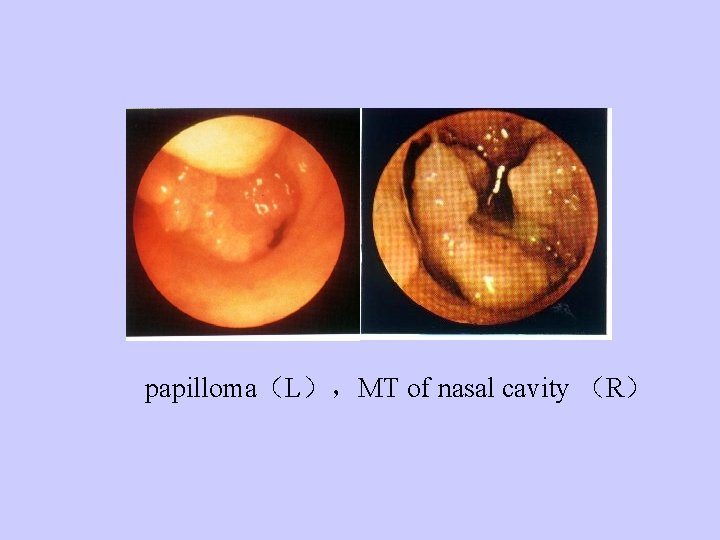

papilloma(L),MT of nasal cavity (R)